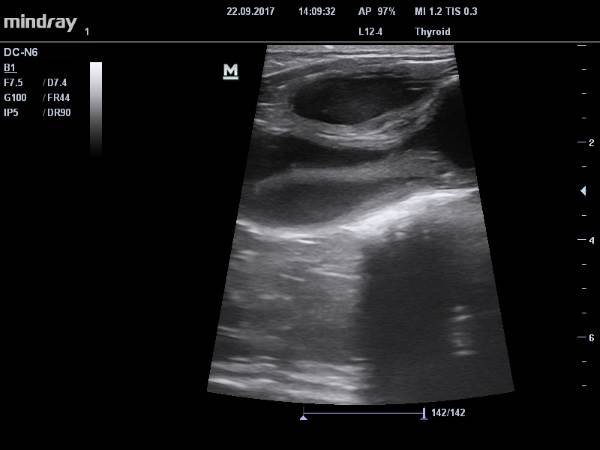

Если доктор считает, что причиной ухудшения самочувствия собаки может быть пиометра, он обязан объяснить владельцам, как важно провести ультразвуковое исследование матки и сделать мазок со слизистой влагалища собаки. При пиометре на УЗИ сразу же будут видны характерные изменения в эндометрии, а также просвет и жидкостное содержимое в полости рогов матки. Вагинальная цитология определяет фазу полового цикла собаки и наглядно демонстрирует уровень воспалительного процесса. Это два быстрых и необходимых исследования, позволяющих установить точный диагноз в кратчайшие сроки и незамедлительно начать лечение собаки.

Самый лучший способ исключить или подтвердить пиометру — это УЗИ репродуктивного тракта. Если исследование проводит врач-репродуктолог, кроме размеров измененного органа будут оценены яичники (к сожалению, если матка сильно расширена яичники можно увидеть не всегда) и краниальная часть влагалища, мочевыделительная система. Врач сразу будет искать ответ на вопрос — почему же так случилось. Порой причиной пиометры становится гормонпродуцирующая опухоль яичника, что может в корне изменить тактику лечения.

Чтобы не спутать пиометру у собаки или кошки с гнойным воспалением влагалища, необходимо провести рентгеновское и ультразвуковое исследование. Ветеринарный врач диагностирует увеличение матки и наличие в ее полости инородного содержимого (не характерного для беременности). На УЗИ же ветврач сможет увидеть гиперплазию эндометрия.

Ультразвуковые исследования «увидят» увеличение матки и рогов матки. Увеличение может быть минимальным или существенным. Увеличение обычно симметрично, но могут возникнуть сегментарные или очаговые изменения. Содержимое просвета обычно однородно и может быть безэховым с сильным дистальным усилением. Ткани могут быть эхогенными, и в этом случае часто отмечается движение, характеризующееся медленными закрученными узорами.

Могут быть отмечены внутрипросветные очаговые гиперэхогенные структуры, которые, как полагают, представляют резорбцию плодов и плацентарной ткани. Стенка матки имеет различный внешний вид, от гладкой и тонкой до толстой и нерегулярной. Можно увидеть на УЗИ сегментарные изменения толщины стенок.

Стенка может быть более эхогенной, чем содержимое матки, или относительно гипоэхогенной. Внутри утолщенного эндометрия часто находятся островки безэховых очагов, которые представляют расширенные кистозные железы, извилистые железистые протоки и сосудистые структуры.

Утолщенный эндометрий с кистозными структурами указывает на кистозную гиперплазию эндометрия с пиометрой или без нее. Оценка яичников может показать наличие кист, гипоэхогенных телесных желтков или сложных массовых поражений. Часто, однако, яичники нормальные или не отображаются вообще.

Основной диагностикой пиометры является ультразвуковое исследование репродуктивной системы.

УЗИ брюшной полости

Ультрасонография брюшной полости является предпочтительным методом оценки пациентов на пиометру. Наиболее частым признаком ультразвукового исследования является вздутие матки с анэхогенной или гиперэхогенной жидкостью (, рис. 2, ) .31,32 Утолщенный кистозный эндометрий указывает на сопутствующую кистозную гиперплазию эндометрия.33 У пациенток с разрывом матки в брюшной полости может быть обнаружена свободная жидкость, а сальник может быть гиперэхогенным вследствие бактериального перитонита.

Ультразвуковое исследование брюшной полости также может использоваться для исключения других состояний, которые могут вызвать увеличение матки или выделения из влагалища, например, беременность на ранних сроках.

Рис. 2. Ультрасонографическое изображение увеличенного и извитого рога матки, заполненного анэхогенной или гипоэхогенной жидкостью.